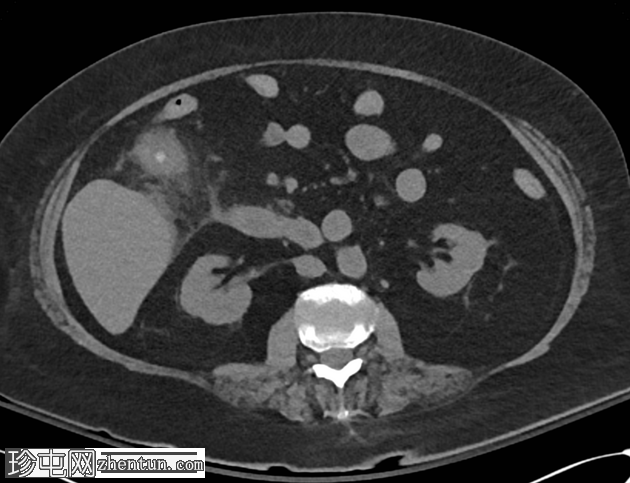

轴位增强扫描

2.png

动脉期

多期CT扫描显示胆囊扩张,内含多发胆结石,胆囊壁增厚,胆囊周围脂肪组织炎症改变,提示急性胆囊炎。可见自发性高密度物质,与出血性内容物相符,符合出血性胆囊炎的影像学表现。

胆囊壁与十二指肠第二段相通,胆囊内可见气体,提示胆囊十二指肠瘘。

动脉期CT显示胆囊内侧缘有一结节状高密度病灶,平扫未见,静脉期CT显示该病灶,符合胆囊假性动脉瘤的影像学表现。